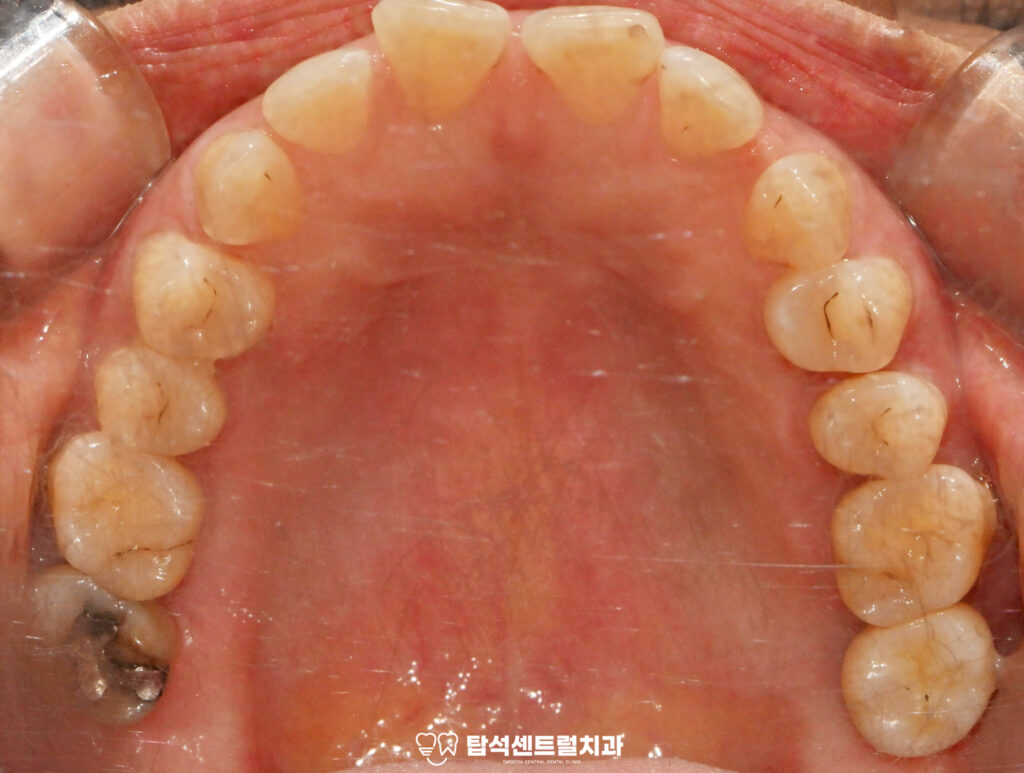

윗니의 경우 발치와 보존술을 시행한 뒤

약 4개월 간 치유 기간을 거쳐

지연 식립 방식으로 진행하는 것이

안전합니다.

해당 방법은 이를 뽑은 자리에

골이식재를 채워 넣어 뼈가 흡수되는

것을 최소화하는 술식을 의미합니다.

흔들리는 18번과 48번 사랑니 역시

발거가 필요한 상태였습니다.

사랑니는 안쪽에 위치해 있어

관리가 어렵고 염증을

유발하기 쉬운데요

다수 치아에서 나타난 치경부 마모증은

레진으로 수복하는 것이 적절합니다.

치경부 마모증은 치아 목 부분이 닳아서

움푹 파인 상태를 말하며,잘못된 칫솔질이나

이갈이 습관으로 발생합니다.